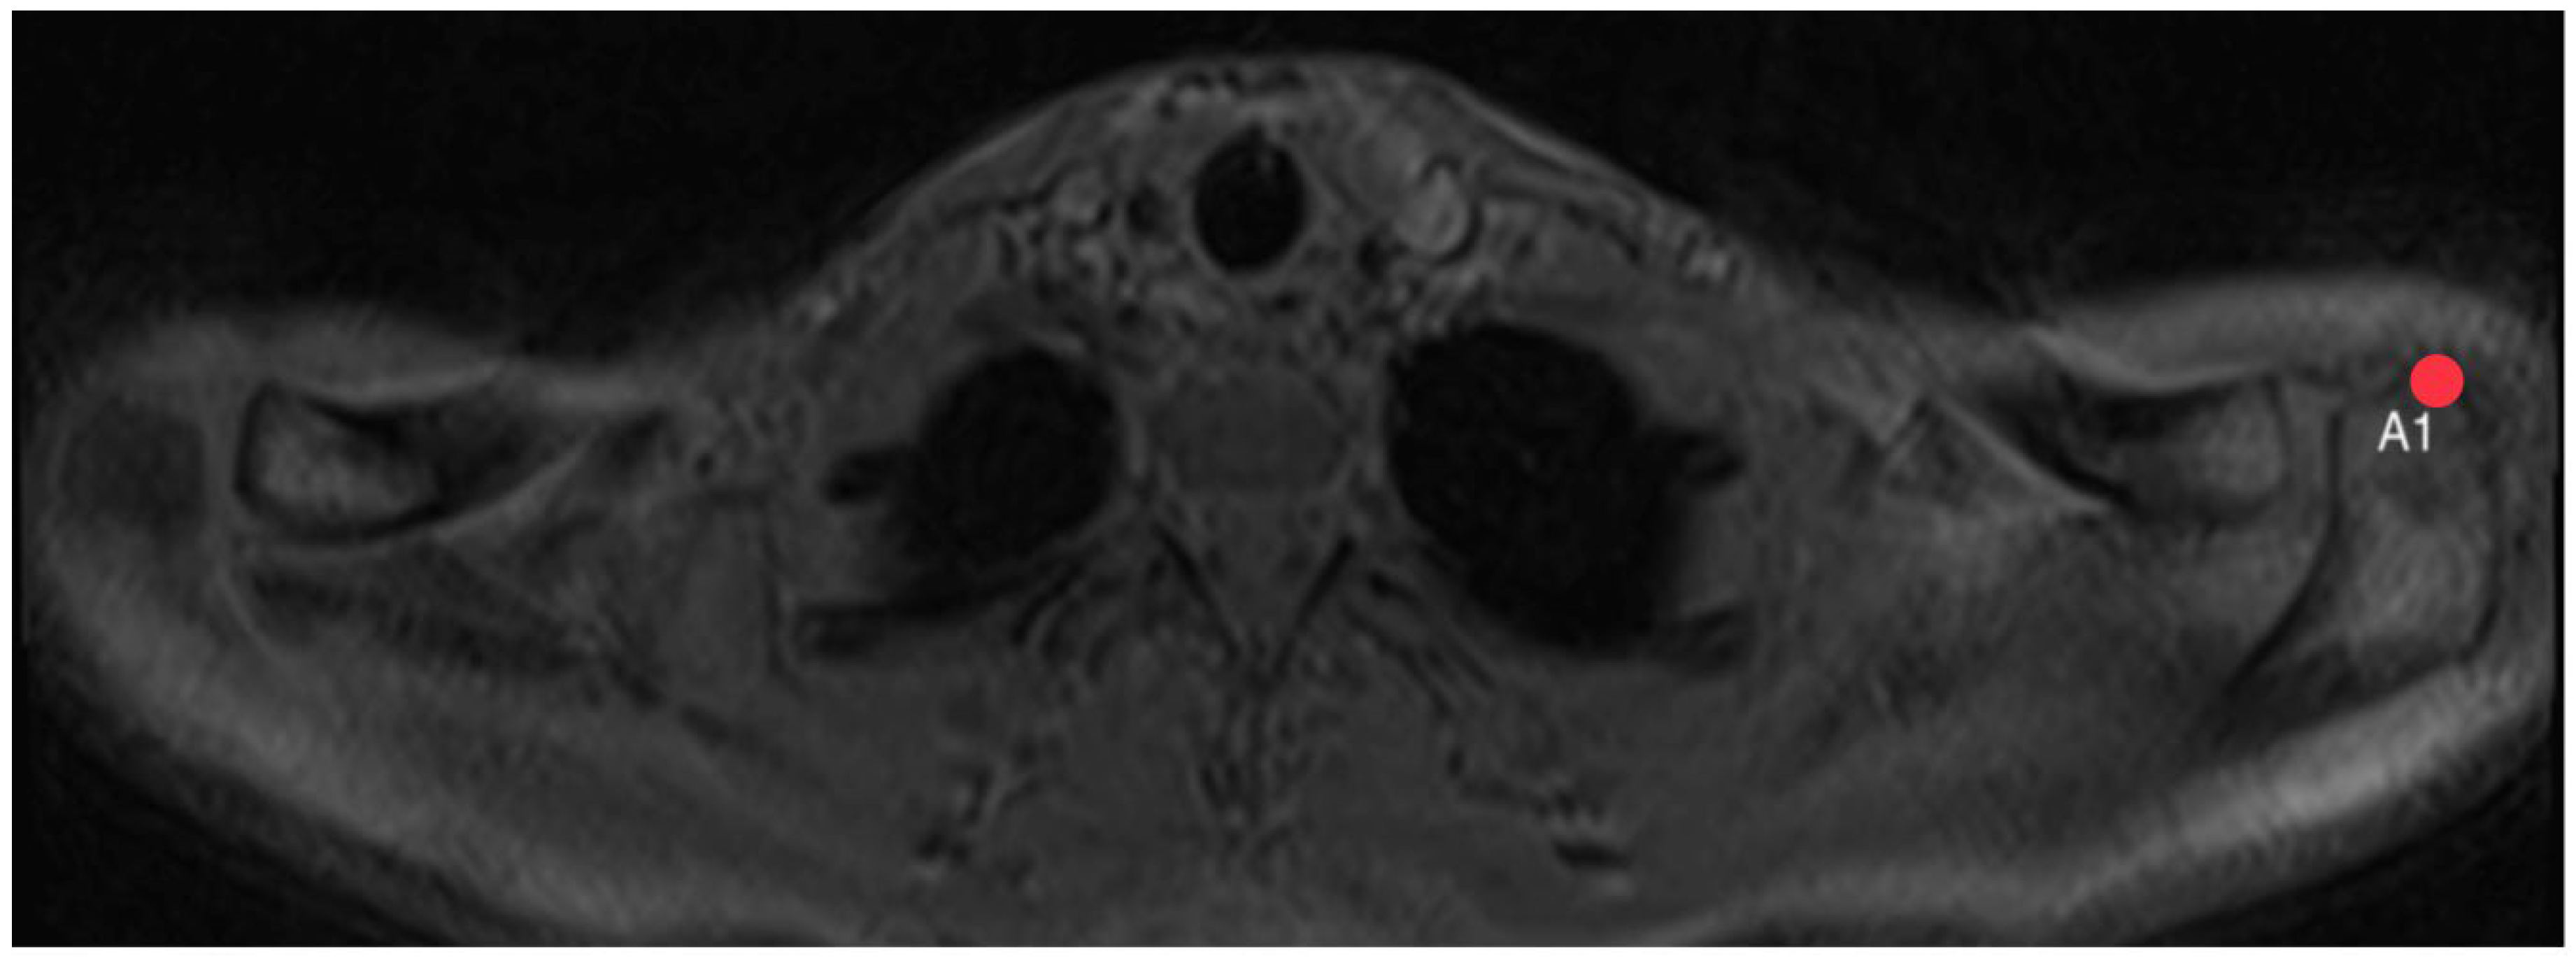

2.4. Acromion Tilt (Figure 6)